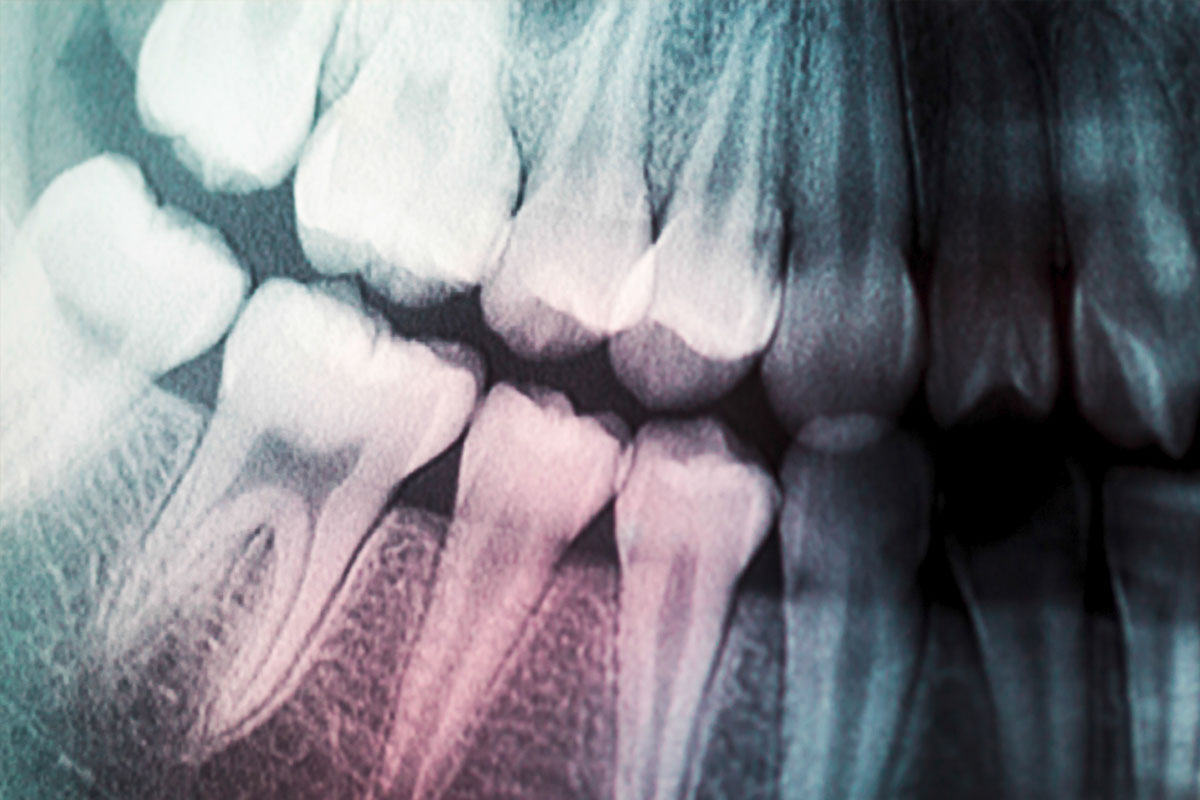

- Periapical X-rays: Focus on a specific tooth. Displays the entire length of the tooth and surrounding bone, aiding in diagnosing dental infections and abscesses.